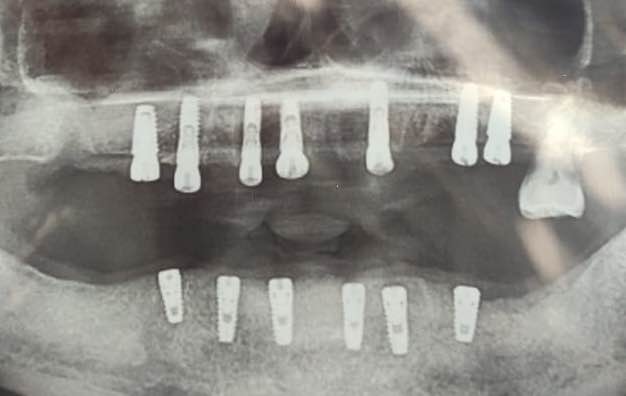

Visit Dr Pandit’s dental and implant center for replacement of missing teeth with dental implants . Dental implants are best option to replace missing teeth helps in better chewing and aesthetics thus improving quality of life and overall health. Visit Dr Pandit’s dental & implant center for dental implants, single visit root canal treatment , cosmetic dentistry, gums treatment. Dr Aashish Pandit MDS, Dr Preeti Kaushik BDS